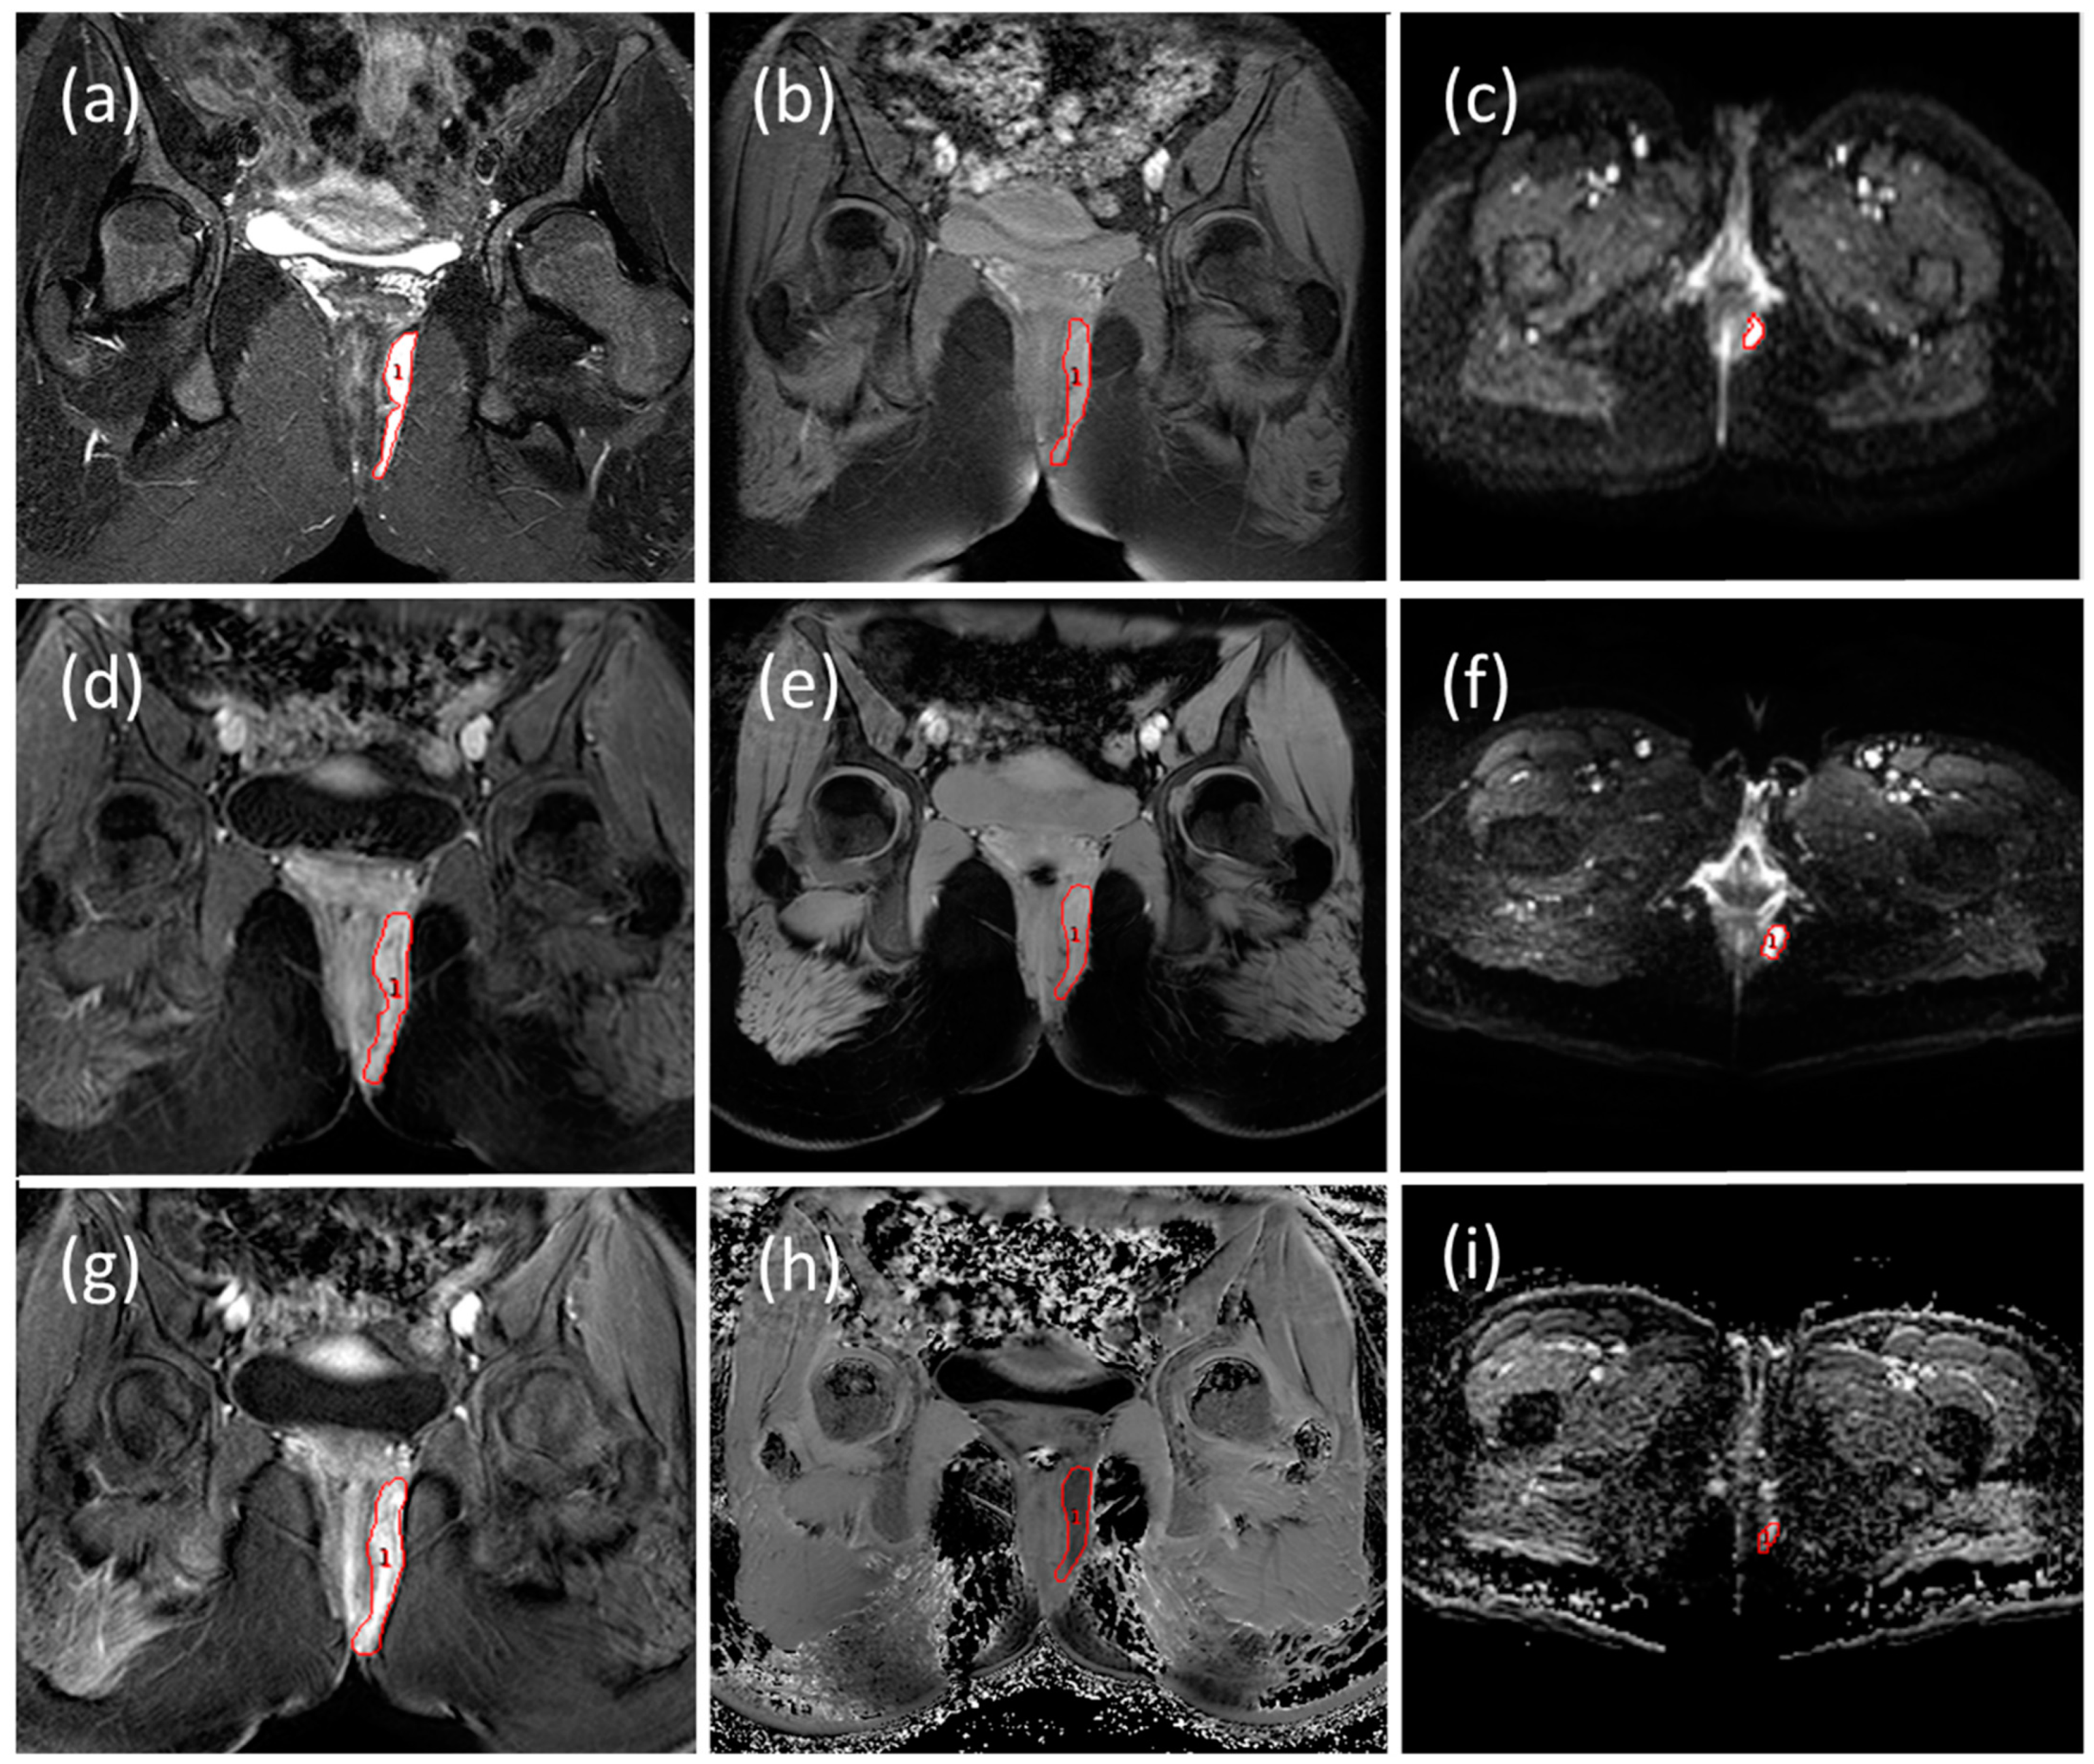

2.3. MRI Image Analysis

2.3.1. Radiological Evaluation